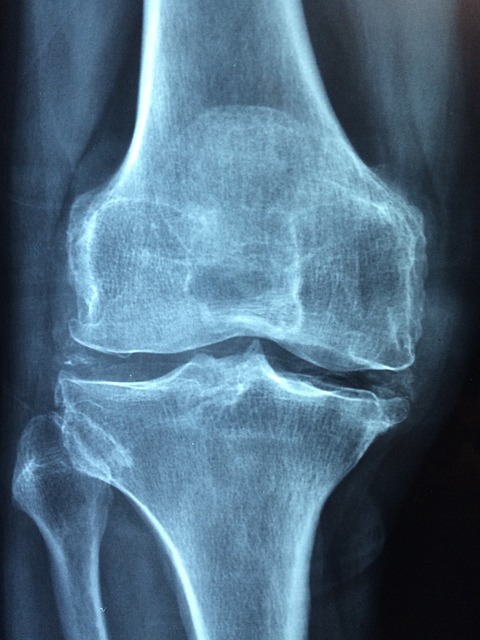

이러한 증상이 있다면 조기에 병원을 찾아 정형외과 진료 및 엑스레이 검사를 받는 것이 중요합니다. 동시에 일상생활 속에서 관절에 무리가 가지 않는 선에서 꾸준히 운동을 병행하면 통증 완화에 도움이 됩니다.